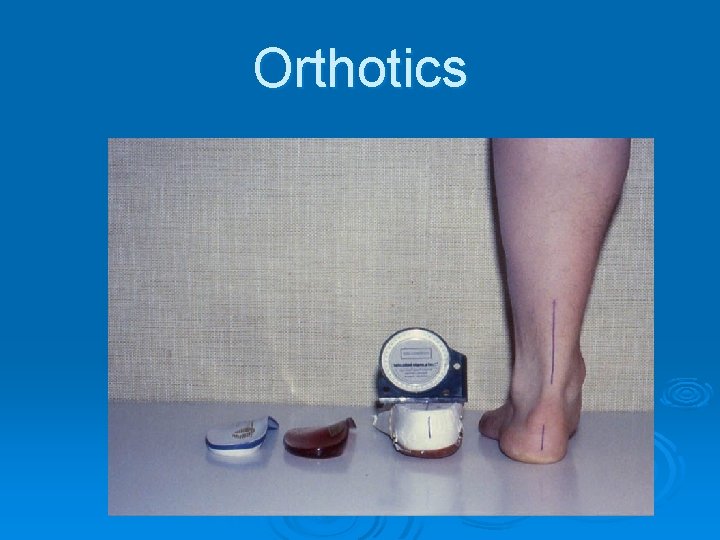

Orthotics

Orthotics

Orthotics